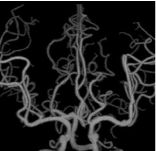

頭部脳血管VR -

頭部脳血管MIP -